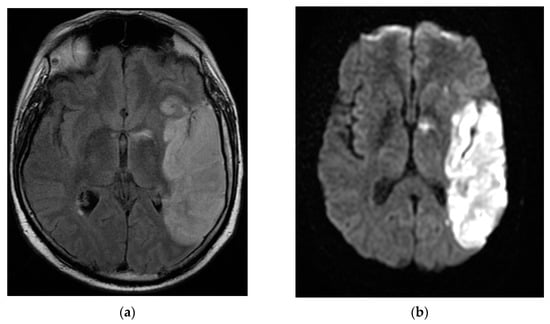

Contrast-enhanced head-computed tomography (head-CT) was conducted upon hospital admission and demonstrated hyperattenuation of the left cavernous sinus and left lateral sinus, which was concerning for sinus thrombosis. MRI of the brain and orbits with and without contrast, in addition to magnetic resonance angiography (MRA)/magnetic resonance venography (MRV) of the head, showed an inflammatory process in the areas of the left cavernous sinus and orbital apex with perineural enhancement surrounding the left optic nerve sheaths. The presence of thrombus in the cavernous sinus was refuted by cerebral MRA/MRV. No vascular malformation of the left internal carotid artery was found. The MRI findings were suggestive of Tolosa–Hunt syndrome (Figure 1).

Figure 1.

MRI T2 axial Flair (a) and coronal T1 FSE (b) images demonstrated perineural tissue extending into the left cavernous sinus. Postcontrast T1 axial FSE (c) and coronal T1 FSE (d) images showed an inflammatory process involving the left cavernous sinus and orbital apex with perineural enhancement surrounding the left optic nerve sheath. MRI: magnetic resonance imaging; Flair: fluid attenuated inversion recovery; FSE: fast spin-echo.